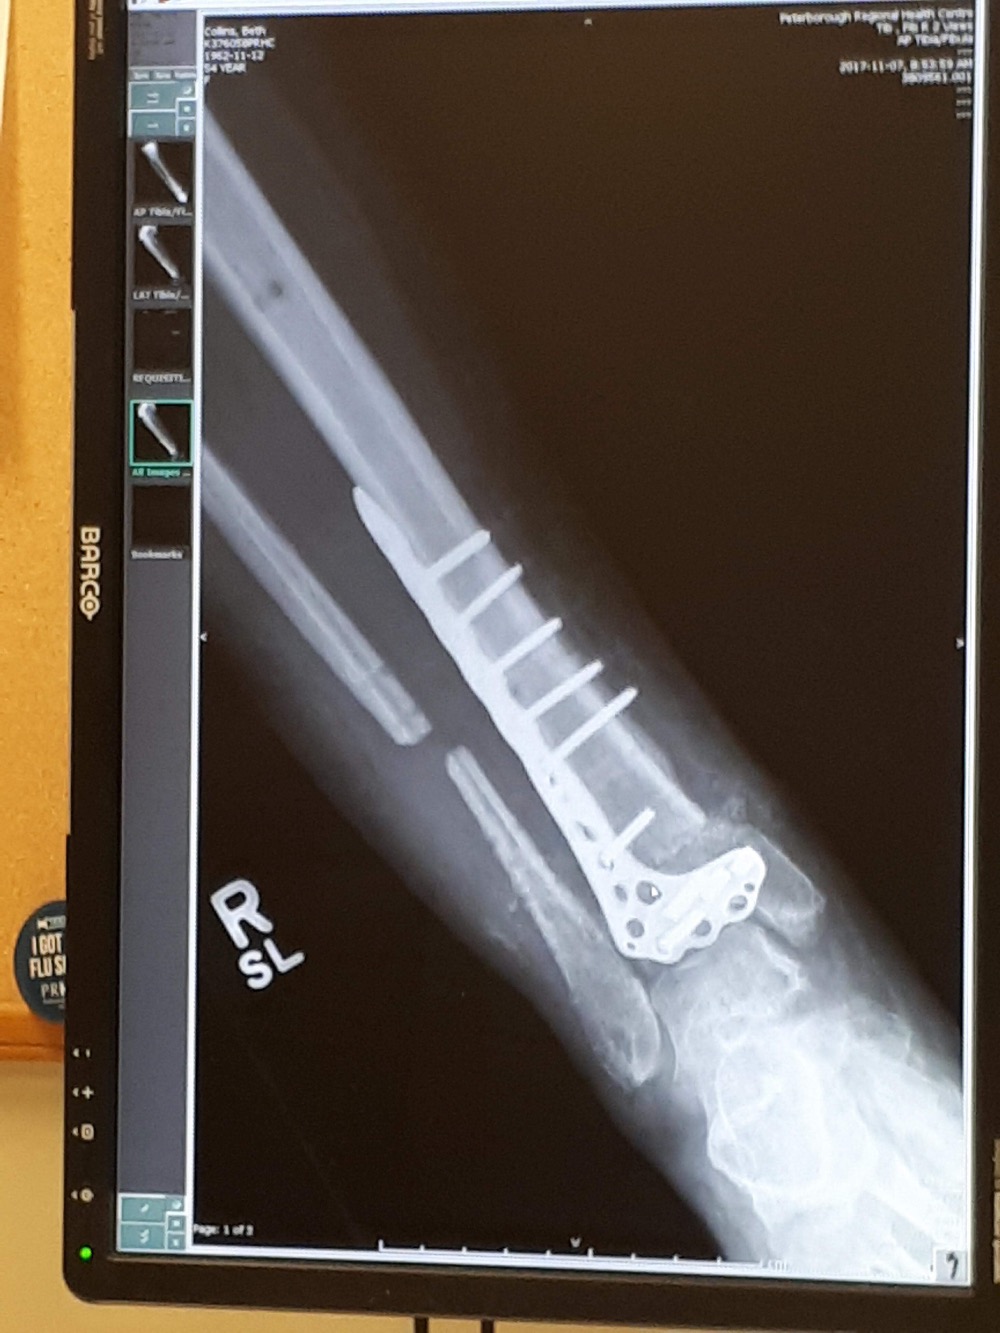

An x-ray of Beth Collins’ leg.

Collins’ right ankle shattered into eight pieces; the fibula and tibia also snapped.

Following 10 surgeries and a bone graft that was unsuccessful, infection set into her leg last November.